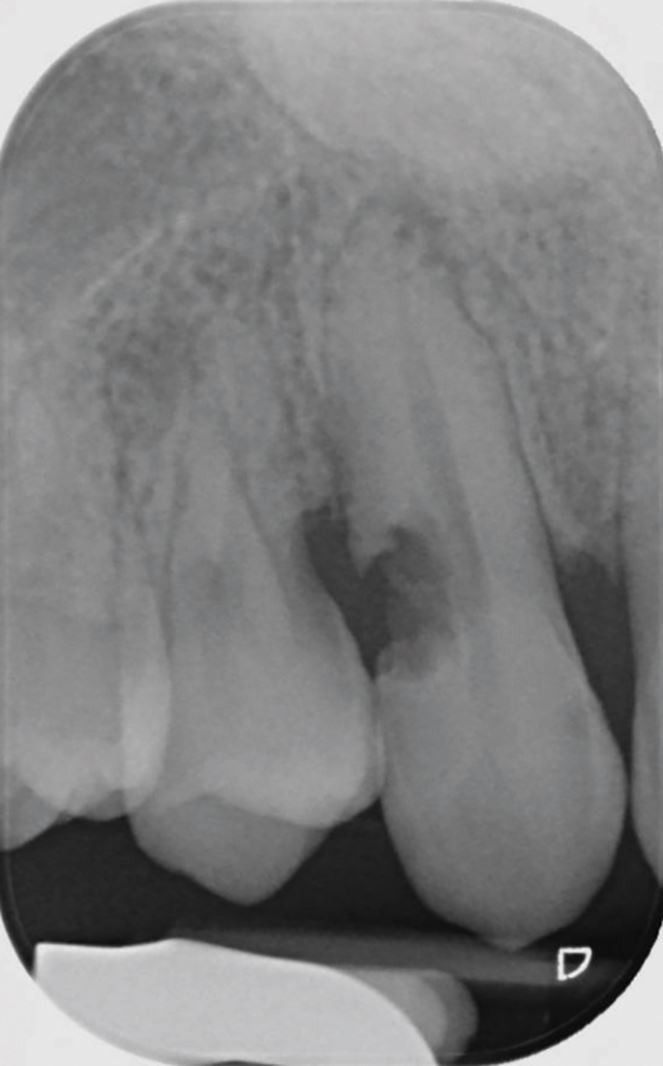

Delays in treatment may occur from athlete behaviour (late arrival, underestimating urgency, uncooperativeness) and healthcare factors (staff knowledge, accident and emergency department waits, triage). Effective care follows three phases: acute (within three hours), subacute (24 hours), and delayed (over 24 hours), as categorised by Andreasen et al.,43 to be followed alongside IADT guidelines34,35,36,37 for structured management (Table 3; Figures 10, 11, 12, 13, 14, 15, 16 and 17).

A CBCT scan of a root fracture, seen in the sagittal plane